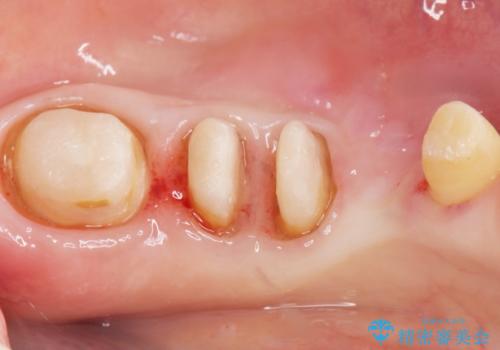

奥歯2本は虫歯により残っている健全歯質が少ないため、保存が難しい状態でした。

虫歯を丁寧に除去した後に歯根を分割し、骨を削合して健全歯質を露出させる骨外科手術を行いました。